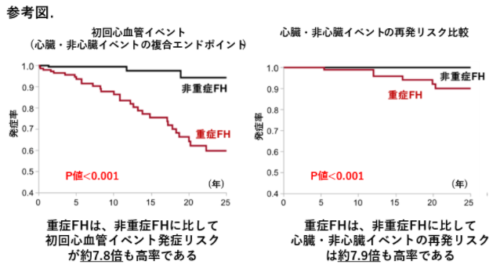

国際動脈硬化学会が策定した "重症"家族性高コレステロール血症 (=severe FH)は、 冠動脈ならびに脳・下肢動脈疾患発症の高リスク群であることを報告

国際動脈硬化学会が策定した"重症"家族性高コレステロール血症 (severe FH)は、冠動脈ならび...